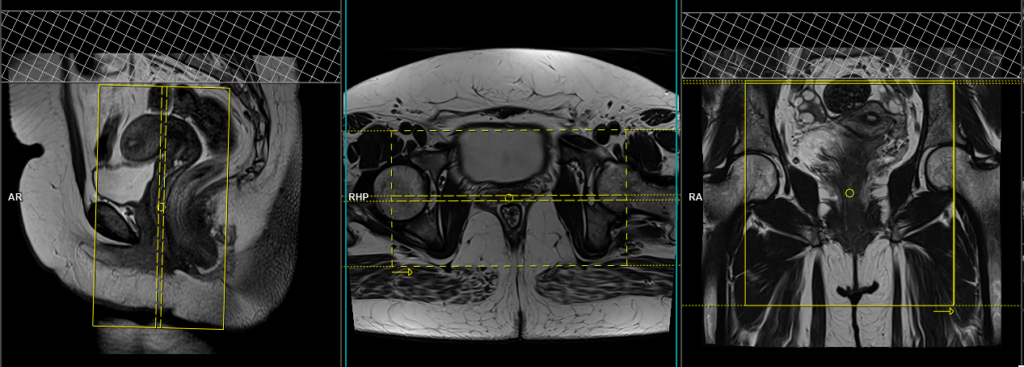

T2 tse fat sat (or stir)coronal oblique 3mm small fov

Plan the coronal slices on the sagittal plane and angle the planning block parallel to the vaginal canal. Check the planning block in the other two planes. An appropriate angle must be given in the axial plane (horizontally across the vagina). Slices must be sufficient to cover the whole rectovaginal area from the pubic symphysis to the sacrum. The field of view (FOV) must be small to produce a high-resolution scan of the rectovaginal area (normally 150 to 200).

Parameters

TR 5000-6000 | TE 110 | FLIP 130 | NEX 5 | SLICE 3 MM | MATRIX 256X256 | FOV 150-200 | PHASE R>L | GAP 10% | FAT SAT SPAIR |